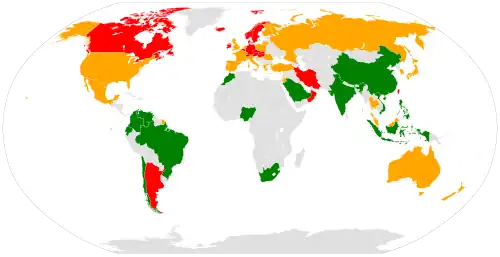

Épidémiologie

- Faible (< 150 / 100 000)

- Moyen (150-250 / 100 000)

- Élevé (> 250 / 100 000)

Les fractures de l'extrémité proximale du fémur sont fréquentes chez les personnes âgées. Elles sont liées à l'ostéoporose, ce qui explique qu'elles frappent plus précocement et plus fréquemment les femmes que les hommes. Elles surviennent souvent après quatre-vingts ans à l'occasion d'un traumatisme minime, telle une chute de sa hauteur. Parfois aussi, elles sont spontanées et entraînent la chute. Leur gravité vient de la fragilité des patients atteints. Globalement un tiers des patients décède dans l'année suivant l'accident, un tiers devient plus ou moins dépendant et seulement un tiers récupère une fonction normale[3]. Aux États-Unis, l'incidence annuelle chez les femmes de plus de 65 ans est légèrement inférieure à 1 %. Elle est de moitié chez les hommes de la même tranche d'âge. Elle a diminué de près de 20 % depuis 1995[4].